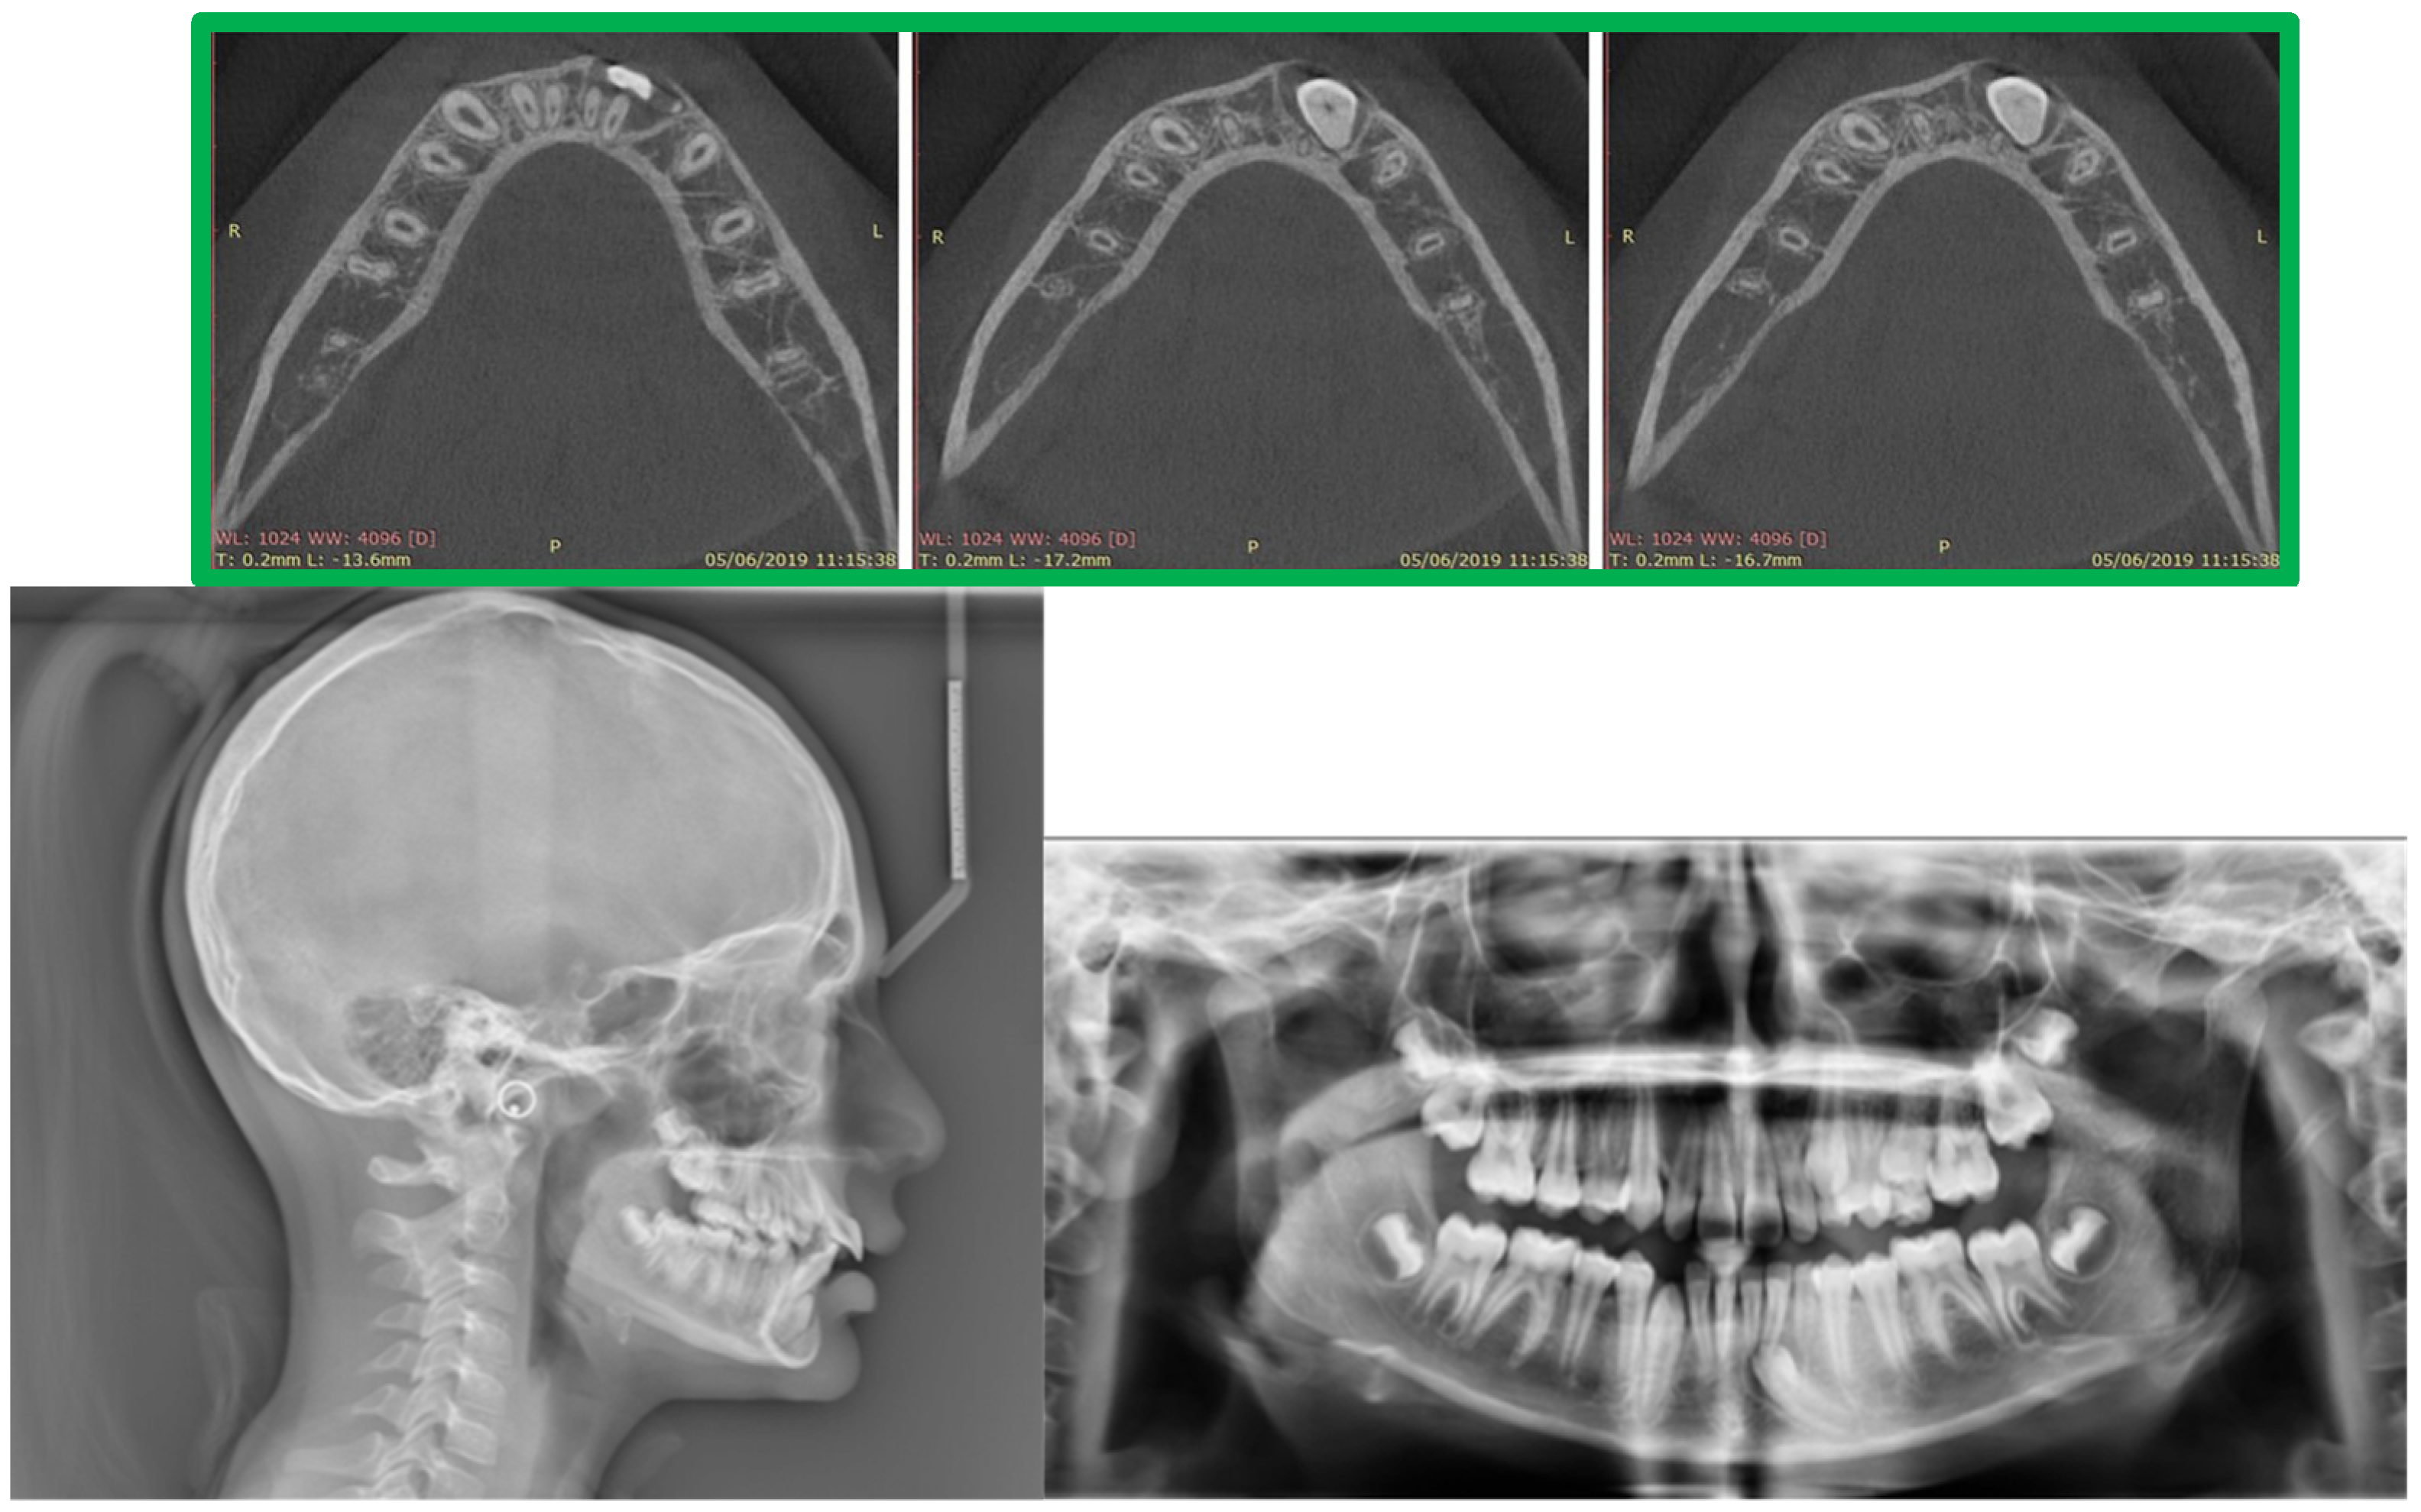

2. Presentation of Case Report

2.2. Treatment Alternatives

- Surgical removal of the impacted tooth and conventional bridge or a fixed prosthesis on implant rehabilitation;

- Auto-transplantation, possibly followed by endodontic treatment of mandibular left canine;

- Surgical exposure of impacted left canine following orthodontic alignment in dental arch [22].

| Measurement | Initial | Final | Norm |

|---|---|---|---|

| S^N^A | 85.2° | 85.5° | 81° |

| S^N^B | 81.3° | 81.8° | 79° |

| A^N^B | 4.2° | 3.7 | 2° |

| SN^Pog | 82.5° | 84.3° | 80° |

| S | 107.7° | 122.8° | 123° ± 5° |

| AR | 168.2° | 143° | 143° ± 6° |

| Go | 106.2 | 111.4° | 130° ± 7° |

| Upper gonial angle | 43.2° | 50° | 52°–55° |

| Lower gonial angle | 63° | 61.3° | 70°–75° |

| N^S^Ar^Go^Gn | 382.1° | 377.2° | 396° |

| Sn/Go-Me | 22.2° | 17.1° | 32° |

| SN | 67.6 mm | 69.7 mm | 71 mm |

| GoMe | 72.3 mm | 78.3 mm | 71 mm |

| S-Ar | 41.3 mm | 32.6 mm | 32 mm |

| Ar-Go | 33.1 mm | 53.8 mm | 44 mm |

| Dentoalveolar component | |||

| UI^SN | 116.15° | 113.37° | 102° ± 2° |

| LI^GOME | 109.72° | 114.5° | 90° ± 3° |

| Interincisal angle | 111.98° | 115.07° | 135° |